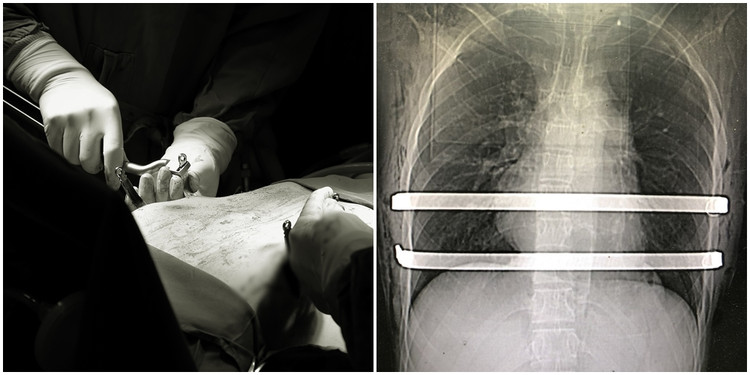

| Vùng ngực lõm nặng, hõm sâu kéo thành rãnh dài dọc xương ức, Kíp bác sĩ khoa Ngoại đặt thanh nâng lõm ngực dưới sự hỗ trợ của hệ thống nội soi - Ảnh BVCC |

BSCKII Phạm Việt Hùng, Trưởng khoa Ngoại, Bệnh viện Đa khoa tỉnh, cho biết: “Với trường hợp của bệnh nhân U. bị lõm ngực bẩm sinh từ nhỏ, đến nay 18 tuổi tình trạng lõm mức độ nặng, phần ngực lõm bị lệch và kéo dài thành rãnh sâu dọc xương ức khiến thanh niên trẻ hay mệt mỏi, hơi thở ngắn, nông nên khó khăn khi tham gia các hoạt động gắng sức.

Qua hội chẩn đánh giá đây là trường hợp biến dạng rộng cả một vùng ngực, thay vì chỉ đặt 1 thanh nâng như thông thường, chúng tôi quyết định đặt 2 thanh nâng kim loại để đạt hiệu quả điều trị tốt nhất với phần ngực lõm được nâng lên đều, đảm bảo chức năng lồng ngực cũng như tính thẩm mỹ cao.

| Bệnh nhân U. được đặt 2 thanh nâng kim loại để xử trí vùng ngực lõm - Ảnh BVCC |

Ca mổ do kíp bác sĩ khoa Ngoại phối hợp khoa Gây mê hồi sức thực hiện. Dưới sự hỗ trợ của dụng cụ nội soi chuyên dụng, phẫu thuật viên tiến hành luồn 2 thanh kim loại được uốn cong qua đường hầm trước tim sau xương ức để nâng phồng vùng ngực bị lõm. Thanh đỡ được cố định bằng chỉ thép để nẹp bám chặt vào khung sườn. Kiểm tra thanh uốn cố định, không chảy máu, phổi giãn nở tốt.